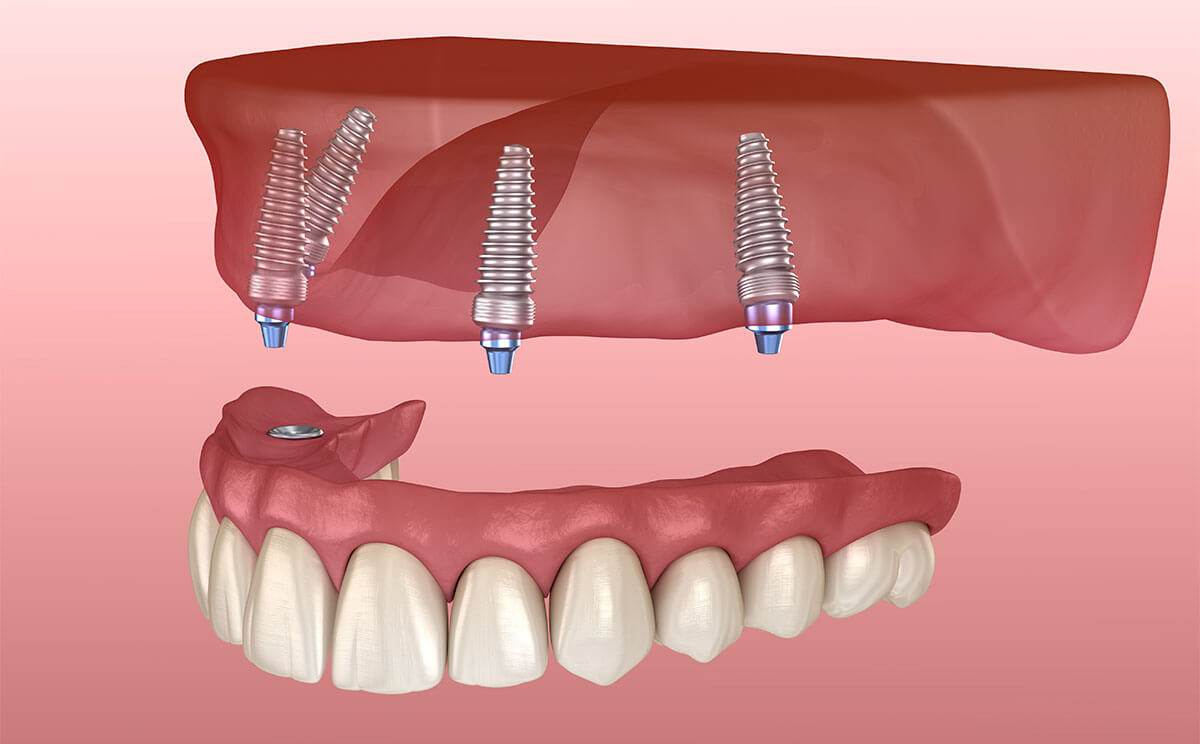

Same-day teeth implants work best when restoring an entire arch or all of your teeth using all-on-four or all-on-six implants. In traditional implant treatment, patients wait months for their implant to integrate into their bone system before receiving a supportive abutment or restoration to replace lost teeth. With teeth in a day, there’s no waiting period between implant placement and getting new teeth.

On the date of your surgery, your dental surgeon will place four or six implants strategically in your mouth to support your new teeth. These implants are placed at an angle within your jaw where your bone is thickest. Once the implants are in place, we’ll attach an arch of fully functional temporary teeth for you until the customized permanent teeth can be made. Your smile is restored in one day rather than waiting months to receive new teeth.